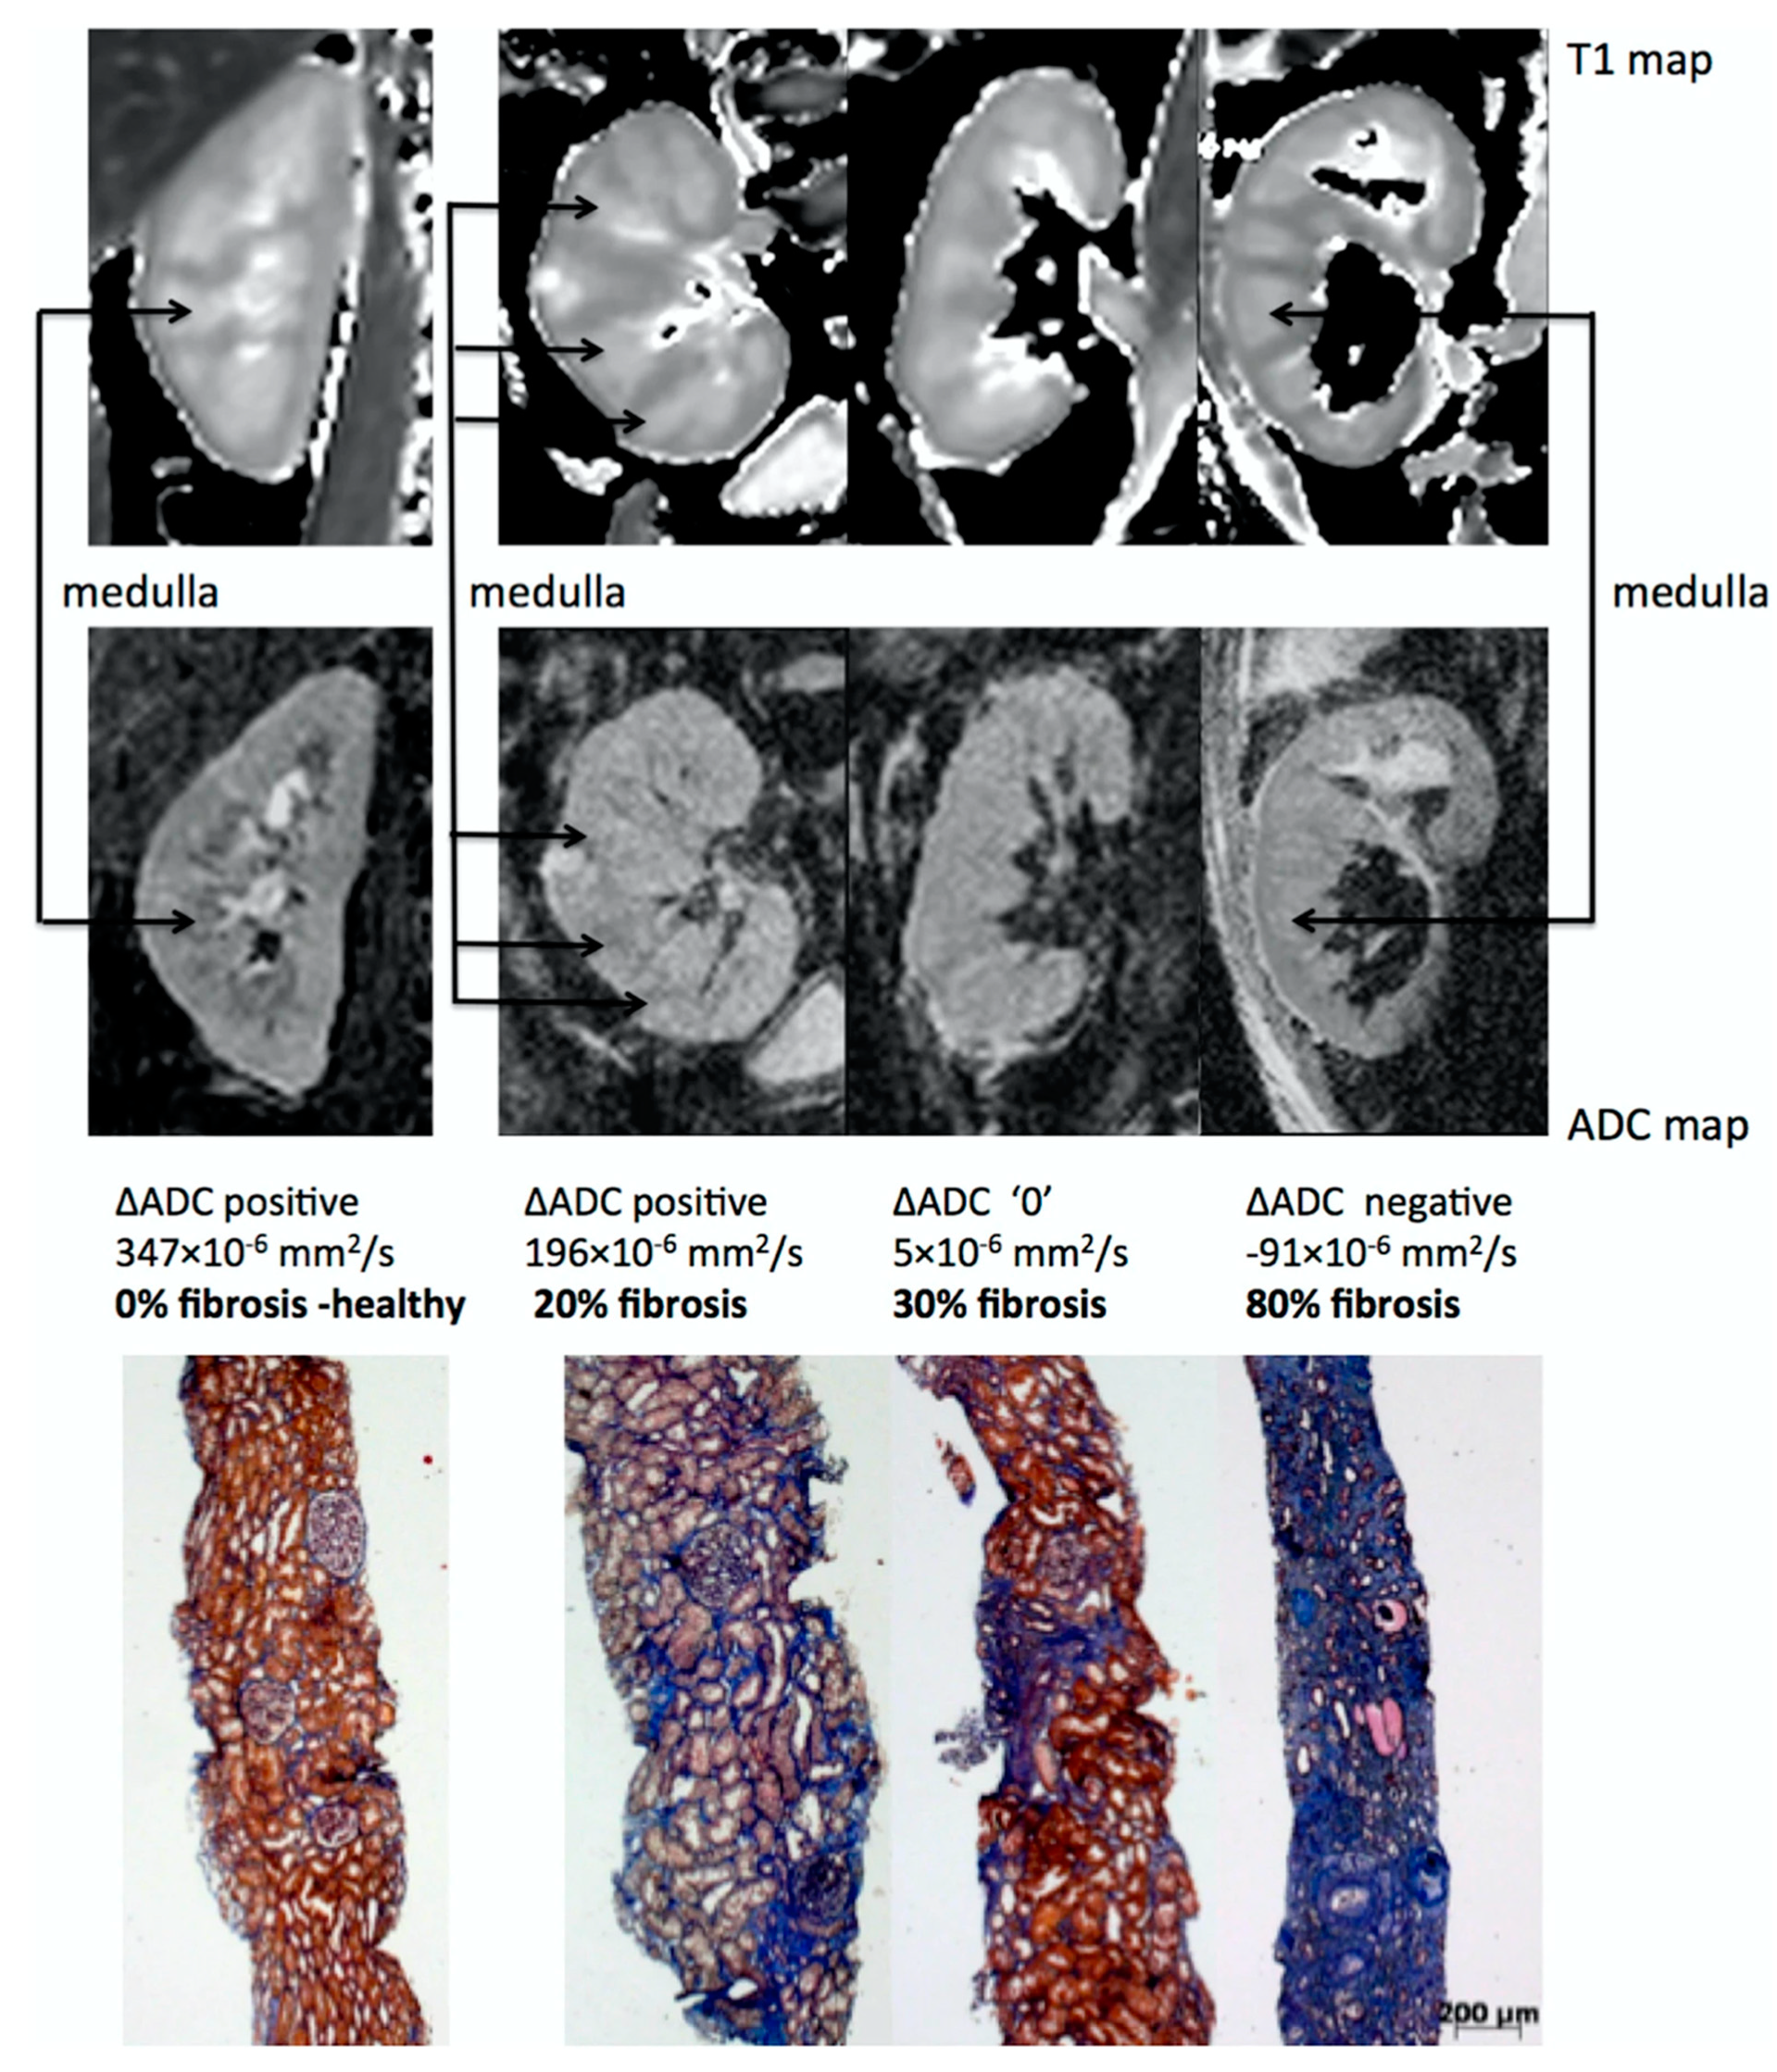

One of the most promising applications of DWI is the estimation of renal fibrosis in chronic kidney disease (CKD) patients, which is a key prognostic marker for renal function decrease and the progression of CKD. This assertion has two main arguments. First, ADC values correlate with renal function [118,119,120,121,122,123] and DWI is an accurate non-invasive imaging technique for the early diagnosis and staging of CKD, as shown by a meta-analysis [124]. Second, numerous clinical studies have directly demonstrated that cortical ADC values as well as other diffusion related parameters are linearly correlated to renal fibrosis in CKD patients, as assessed by renal biopsy [105,125,126,127,128,129,130,131,132,133]. As fibrosis increases, the cortical ADC values decrease much more than the medullary ADC values, resulting in an inversion of the cortico-medullary difference of ADC or so-called ΔADC which can be observed in the images [129] (see Figure 7). DWI can also differentiate between the different levels of fibrosis [127,128].

Figure 7.

Representative biopsy and MR images in chronic kidney disease patients. Morphological MOLLI T1 maps used for the positioning of the regions of interest (top row) and ADC maps (lower row) for three patients showing different ΔADC cases: positive, zero and negative; along with the corresponding fibrosis levels from histology (Masson trichrome staining). The inversion of the corticomedullary ADC difference meets the increasing degree of renal fibrosis. Adapted from Figure 7 of Ref. [129] with permission. Copyright 2016 Springer Nature.

The exact physiological and mechanistic explanation for the link between DWI values and renal fibrosis is not fully understood but may be the result of two main synergetic events occurring in the development of renal fibrosis in CKD: (1) an increase in cellular density and the extra-cellular matrix which reduces free water motion and (2) a reduction of microvascular perfusion and filtration-induced water mobility expected with impaired renal function [134].

Interestingly, the correlation of DWI with renal fibrosis is independent of the renal function as measured by eGFR, further supporting the role of DWI as a surrogate of renal fibrosis [127]. Whether DWI may allow reducing the number of renal biopsies by predicting the amount of interstitial fibrosis in CKD is currently not known and needs further evaluation.